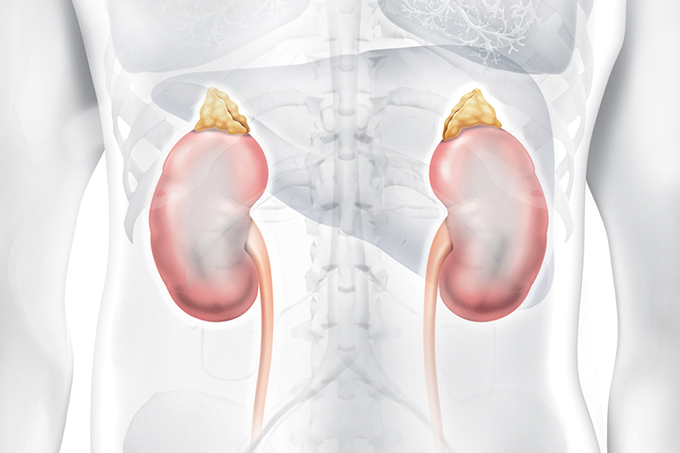

DANOS PÓS-COVID | Coronavírus pode gerar sequelas na função renal e aparelho urogenital

A pandemia do novo coronavírus (Sars-Cov-2) trouxe resultados devastadores para o planeta. Além das mais de 5 milhões de mortes em todo o mundo, os seres humanos ainda precisam lidar com as sequelas causadas pela